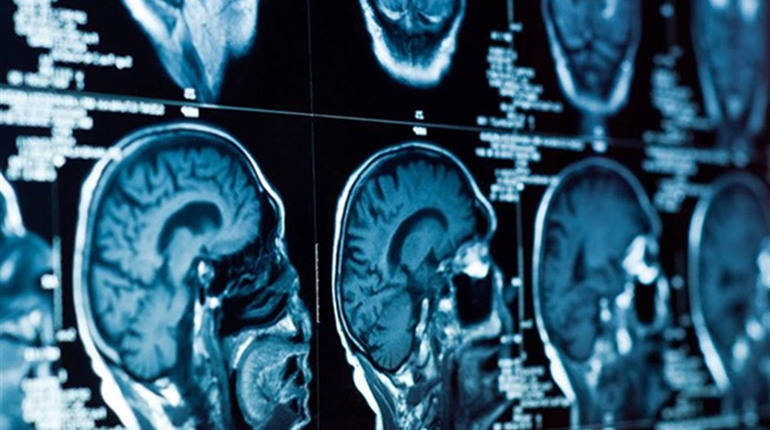

Компьютерная томография является универсальным методом исследования. С ее помощью диагностируют различные заболевания. Чаще всего проводится КТ головного мозга, легких, сосудов, скелетной системы, почек и мочеполовых путей, желудочно-кишечного тракта, костей.

Например, при исследовании мозга специалисты могут выявить опухоль или кровотечение в нем. Обследование скелетной системы дает представление о наличии переломов, грыж, метастазов и опухолей.

В основе метода компьютерной томографии лежит использование рентгеновских лучей. Они позволяют за короткий временной промежуток получить огромное количество рентгеновских снимков исследуемой области. Изображения накапливаются и обрабатываются специальной программой. На их основе специалист может поставить точный диагноз и разработать наиболее эффективную схему лечения.